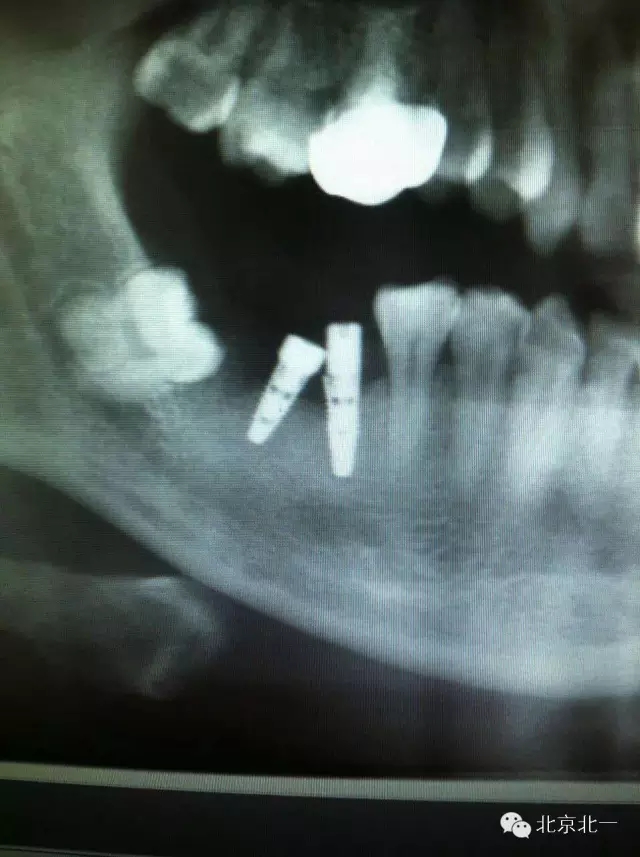

附圖:種植體植入角度不佳導(dǎo)致愈合基臺(tái)無法就位,如果在前牙區(qū)可能帶來美學(xué)更大問題。值得思考。